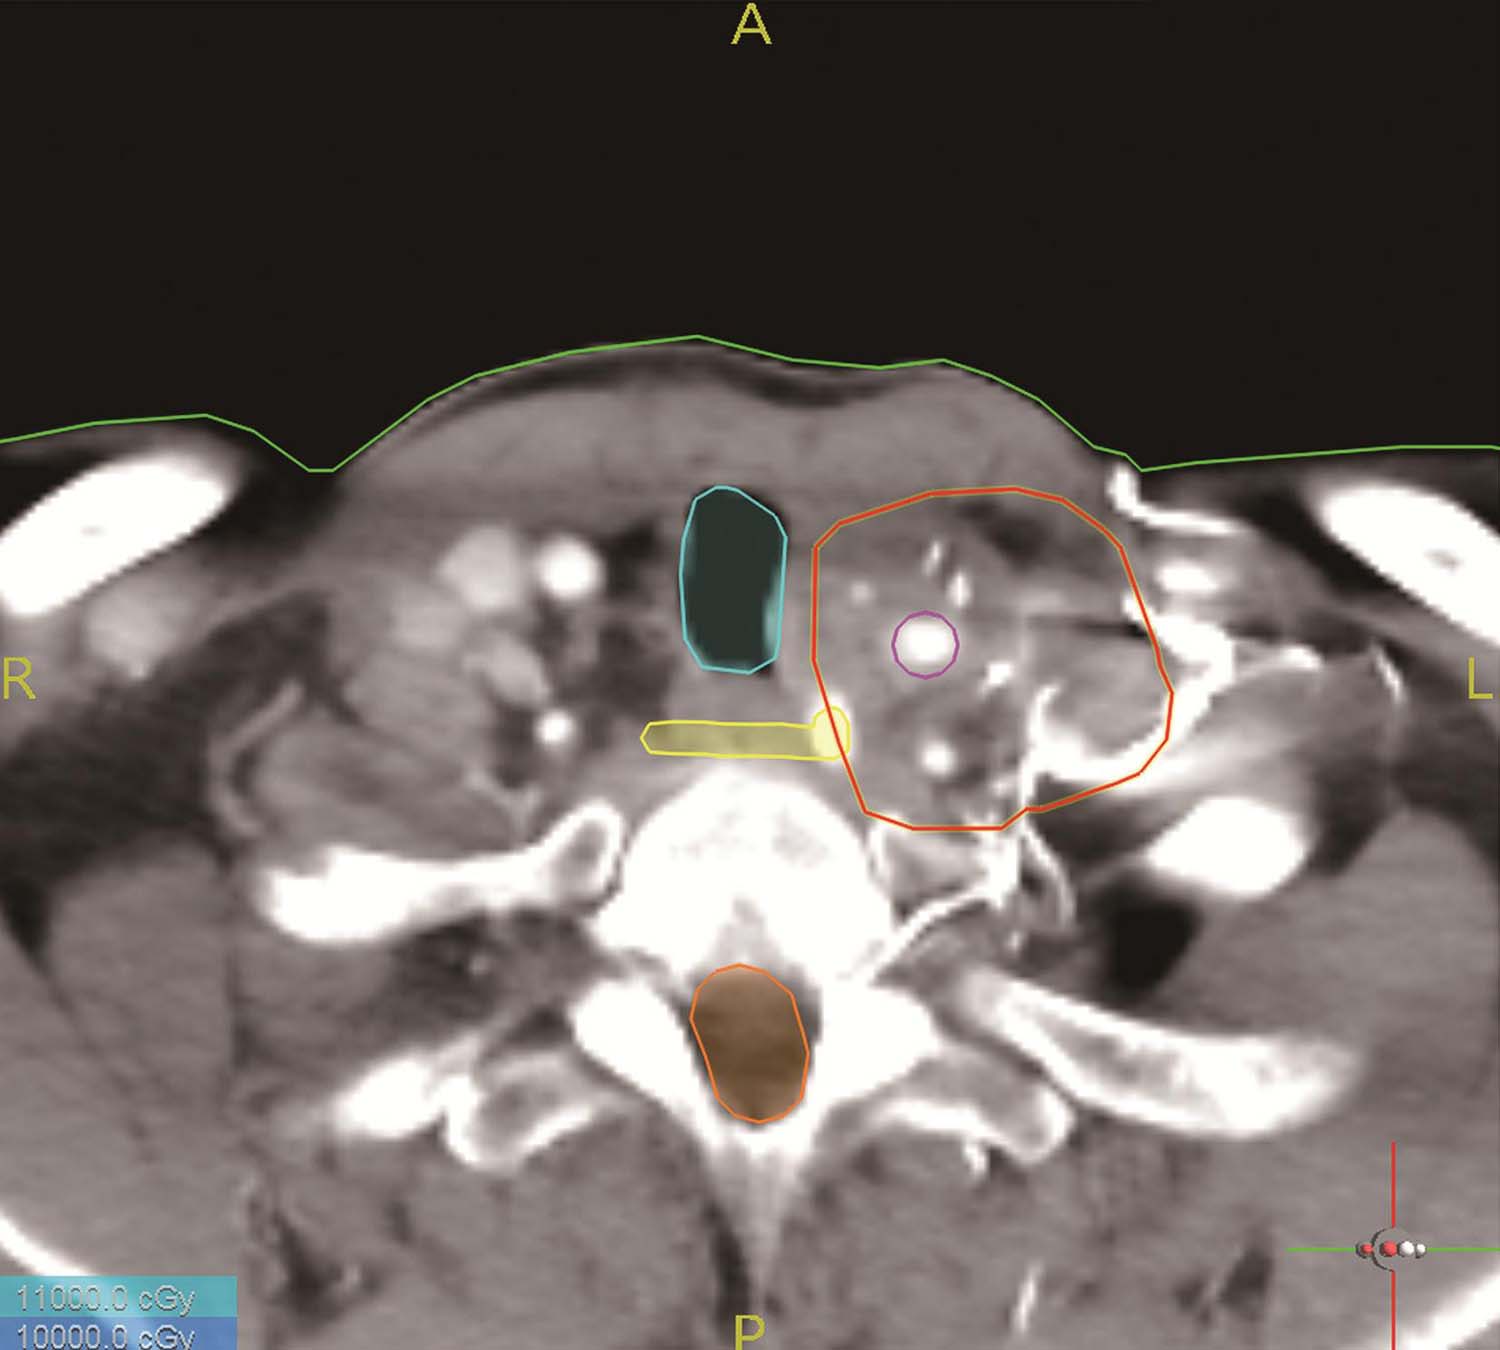

(1)将患者的CT图像传到TPS,选择层厚5mm的CT图像,进行术前计划,临床医师与物理师同时勾画危及器官及肿瘤靶区(GTV),然后根据不同肿瘤的生物学行为及放疗敏感性外扩一定范围得出CTV。

(2)选择合适的粒子活度,根据主管医生所给处方剂量,规划穿刺路径,规避危及器官,设计针道位置,载入粒子,使处方剂量等剂量曲线包绕靶区,避免靶区内冷点和靶区外热点,得出粒子数及DVH图,通过对D 90 、V 90 、V 100 、V 150 、EI、DHI、VI等剂量学参数进行评价。

本步骤为术前计划设计的关键步骤,有如下要点需要特别注意:

1)勾画靶区和危及器官:靶区勾画尽量遵循外放疗原则,如肺肿瘤一定在肺窗勾画靶区,按不同肿瘤生物学行为外扩一定范围形成CTV。同时准确勾画危及器官,包括可能被手术穿刺损伤的器官和可能出现辐射损伤的危及器官(图4-4-2)。

2)三维重建皮肤、骨骼、靶区及危及器官(图4-4-3):大体观察可能的进针路径,首先看是否肿瘤的各部位均可用共面针道穿刺到位,如果不能完全用共面针道解决,则观察可行的非共面针道进针路径。

图4-4-2 勾画危及器官

图4-4-3 三维重建皮肤、靶区及危及器官